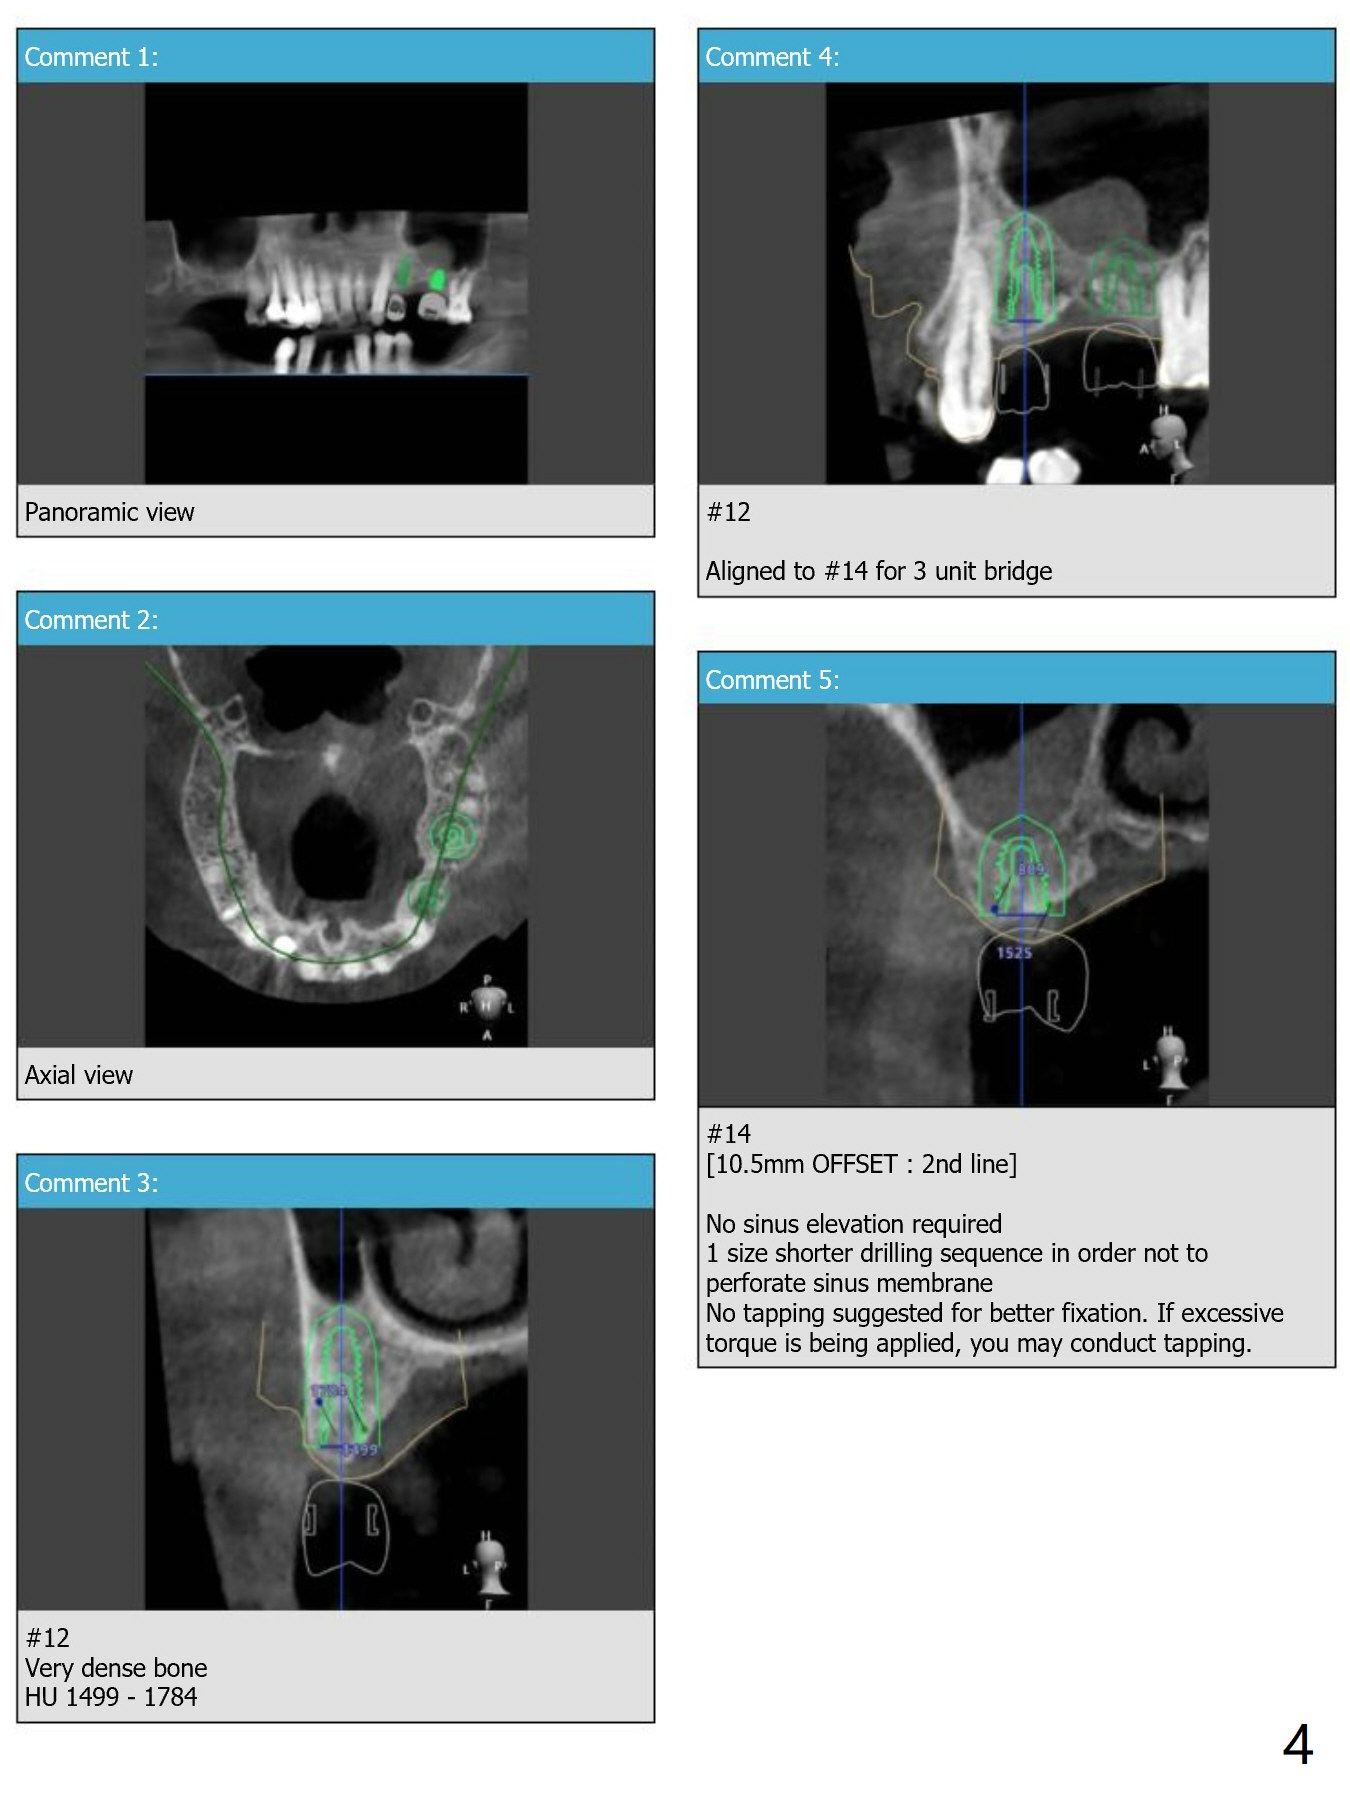

Return to Upper Molar Immediate Implant, Armaments